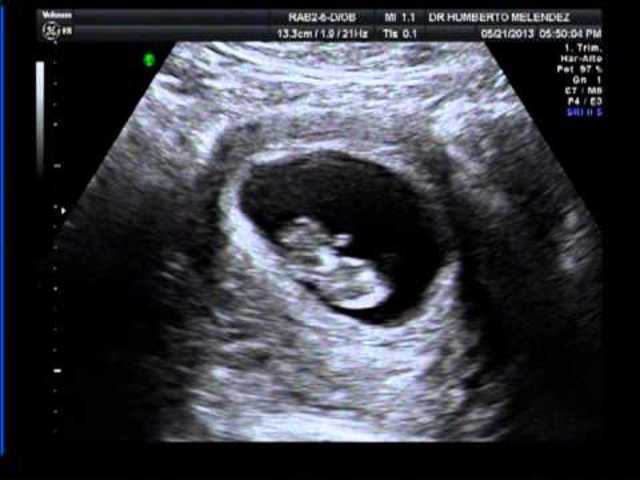

Después del coito, el óvulo y el espermatozoide se fusionan, este proceso se llama fecundación. Ocurre en la ámpula de una de las Trompas de Falopio.

El ovulo fecundado ahora es llamado cigoto y contiene 46 cromosomas. Se segmenta y convierte en Blastocisto y se implanta en el endometrio, tras haber viajado por toda la trompa(5 días).